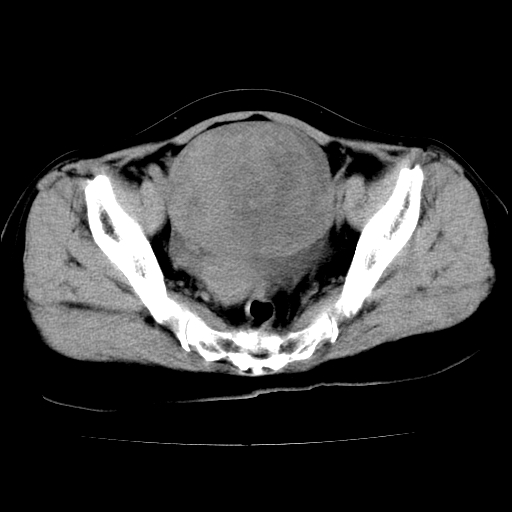

标题: CT24785:女,62岁,发现下腹部肿物半年。 [打印本页]

女,62岁,发现下腹部肿物半年,下腹部不适。

考虑回肠间质瘤,不排除卵巢癌可能。

支持卵巢癌

该年龄性别首先考虑平滑肌肉瘤可能性大,其他待排除。